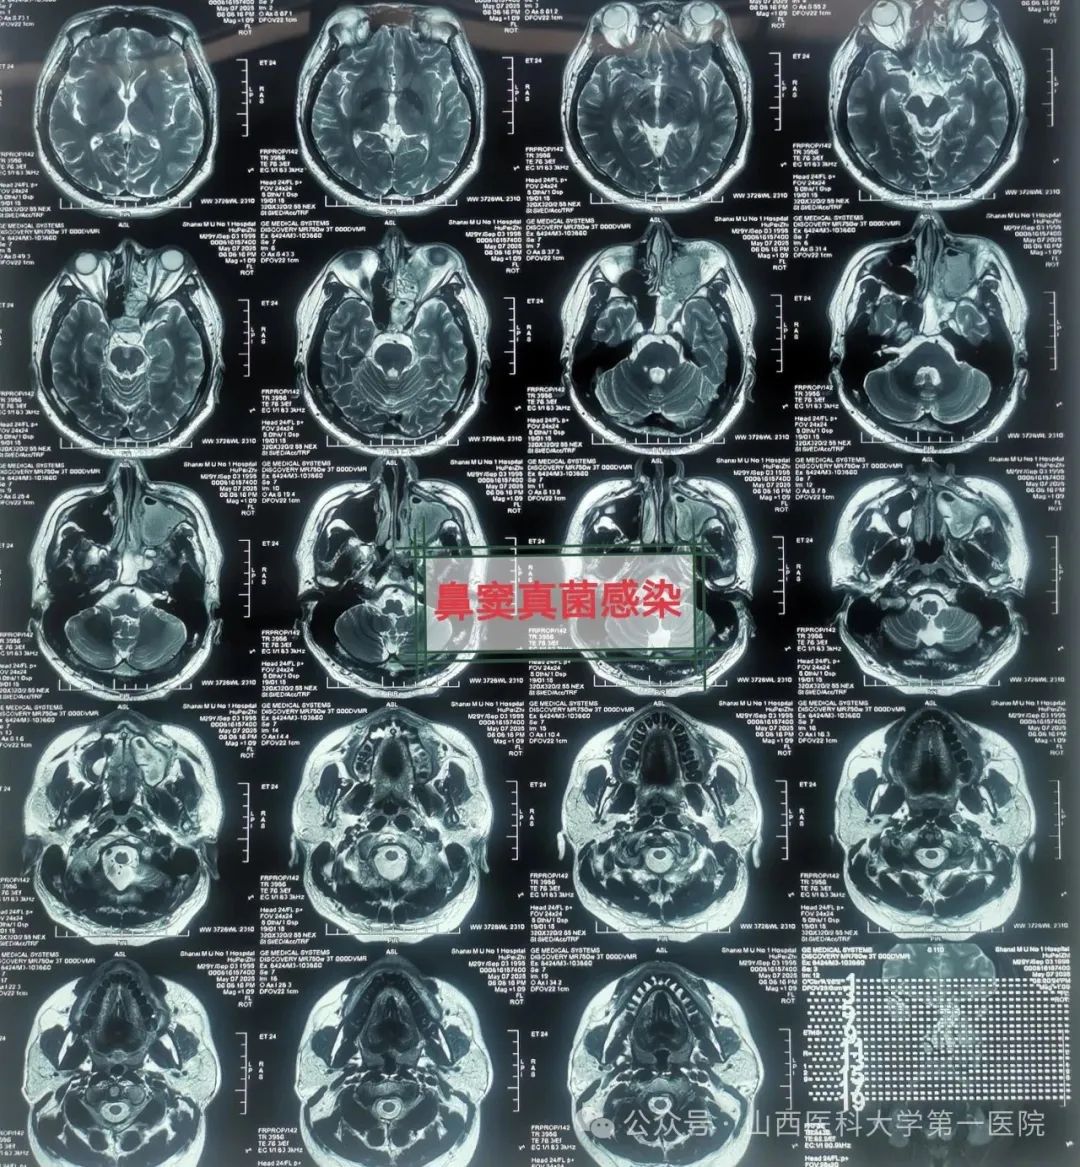

49岁的袁先生过敏性鼻炎多年,合并糖尿病与痛风,一直药物维持治疗;2年前因合并鼻窦炎,口服药物治疗效果不佳;近数月以来病情逐渐加重,鼻塞流涕,最近头痛头闷症状越来越严重同时出现鼻涕带血丝,就诊于51风流

耳鼻咽喉-头颈外科,确诊为鼻窦真菌感染,医生通过手术切除鼻腔病变组织,清除霉菌团块,开放鼻窦,引流分泌物,清洗术腔,重建鼻腔结构、恢复功能,改善并缓解了临床症状。

耳鼻咽喉-头颈外科皇甫辉教授介绍,真菌性鼻窦炎是临床常见的特异性感染性疾病,近年来发病率有上升趋势,可能与抗生素广泛使用、环境污染等有关,而糖尿病、抗肿瘤药物治疗、放疗以及长期使用激素等是真菌性鼻窦炎的高发人群。真菌性鼻窦炎通常分非侵袭型真菌性鼻-鼻窦炎与侵袭型真菌性鼻-鼻窦炎两类,非侵袭型真菌性鼻-鼻窦炎之病变局限在鼻窦腔内,粘膜和骨壁内却无真菌侵犯;而侵袭型真菌性鼻-真窦炎是真菌感染不仅位于鼻腔,同时侵犯鼻窦粘膜和骨壁,并向鼻窦外周围结构和组织如眼眶、前颅底或翼腭窝等侵袭发展,一般情况下,侵袭型真菌性鼻-真窦炎预后凶险。